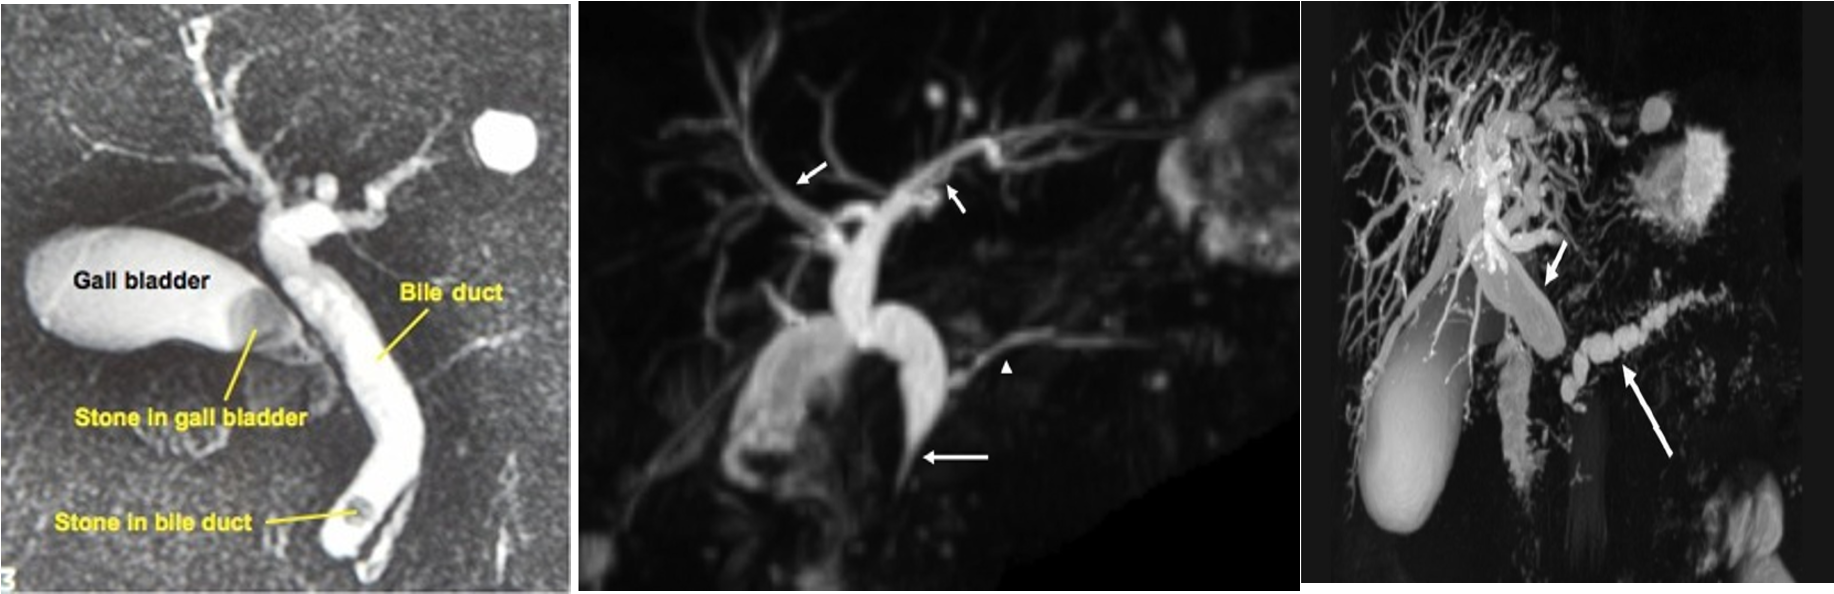

b) Magnetic resonance imaging (MRI): magnetic resonant cholangiopancreatography (MRCP) is non-invasive tool to assess the biliary system. MRI can assess for any lesion causing biliary obstruction such as pancreatic tumor or cholangiocarcinoma.

MRCP showing stone in the common bile duct and in the gallbladder

MRCP study - stone in GB z

Double duct sign and stricture at the lower end of CBD strongly suggest carcinoma of pancreas

-

Note: Double duct sign Z shows that CBD and PD are both dilated

The width of a normal pancreatic duct is 3â4 mm Z